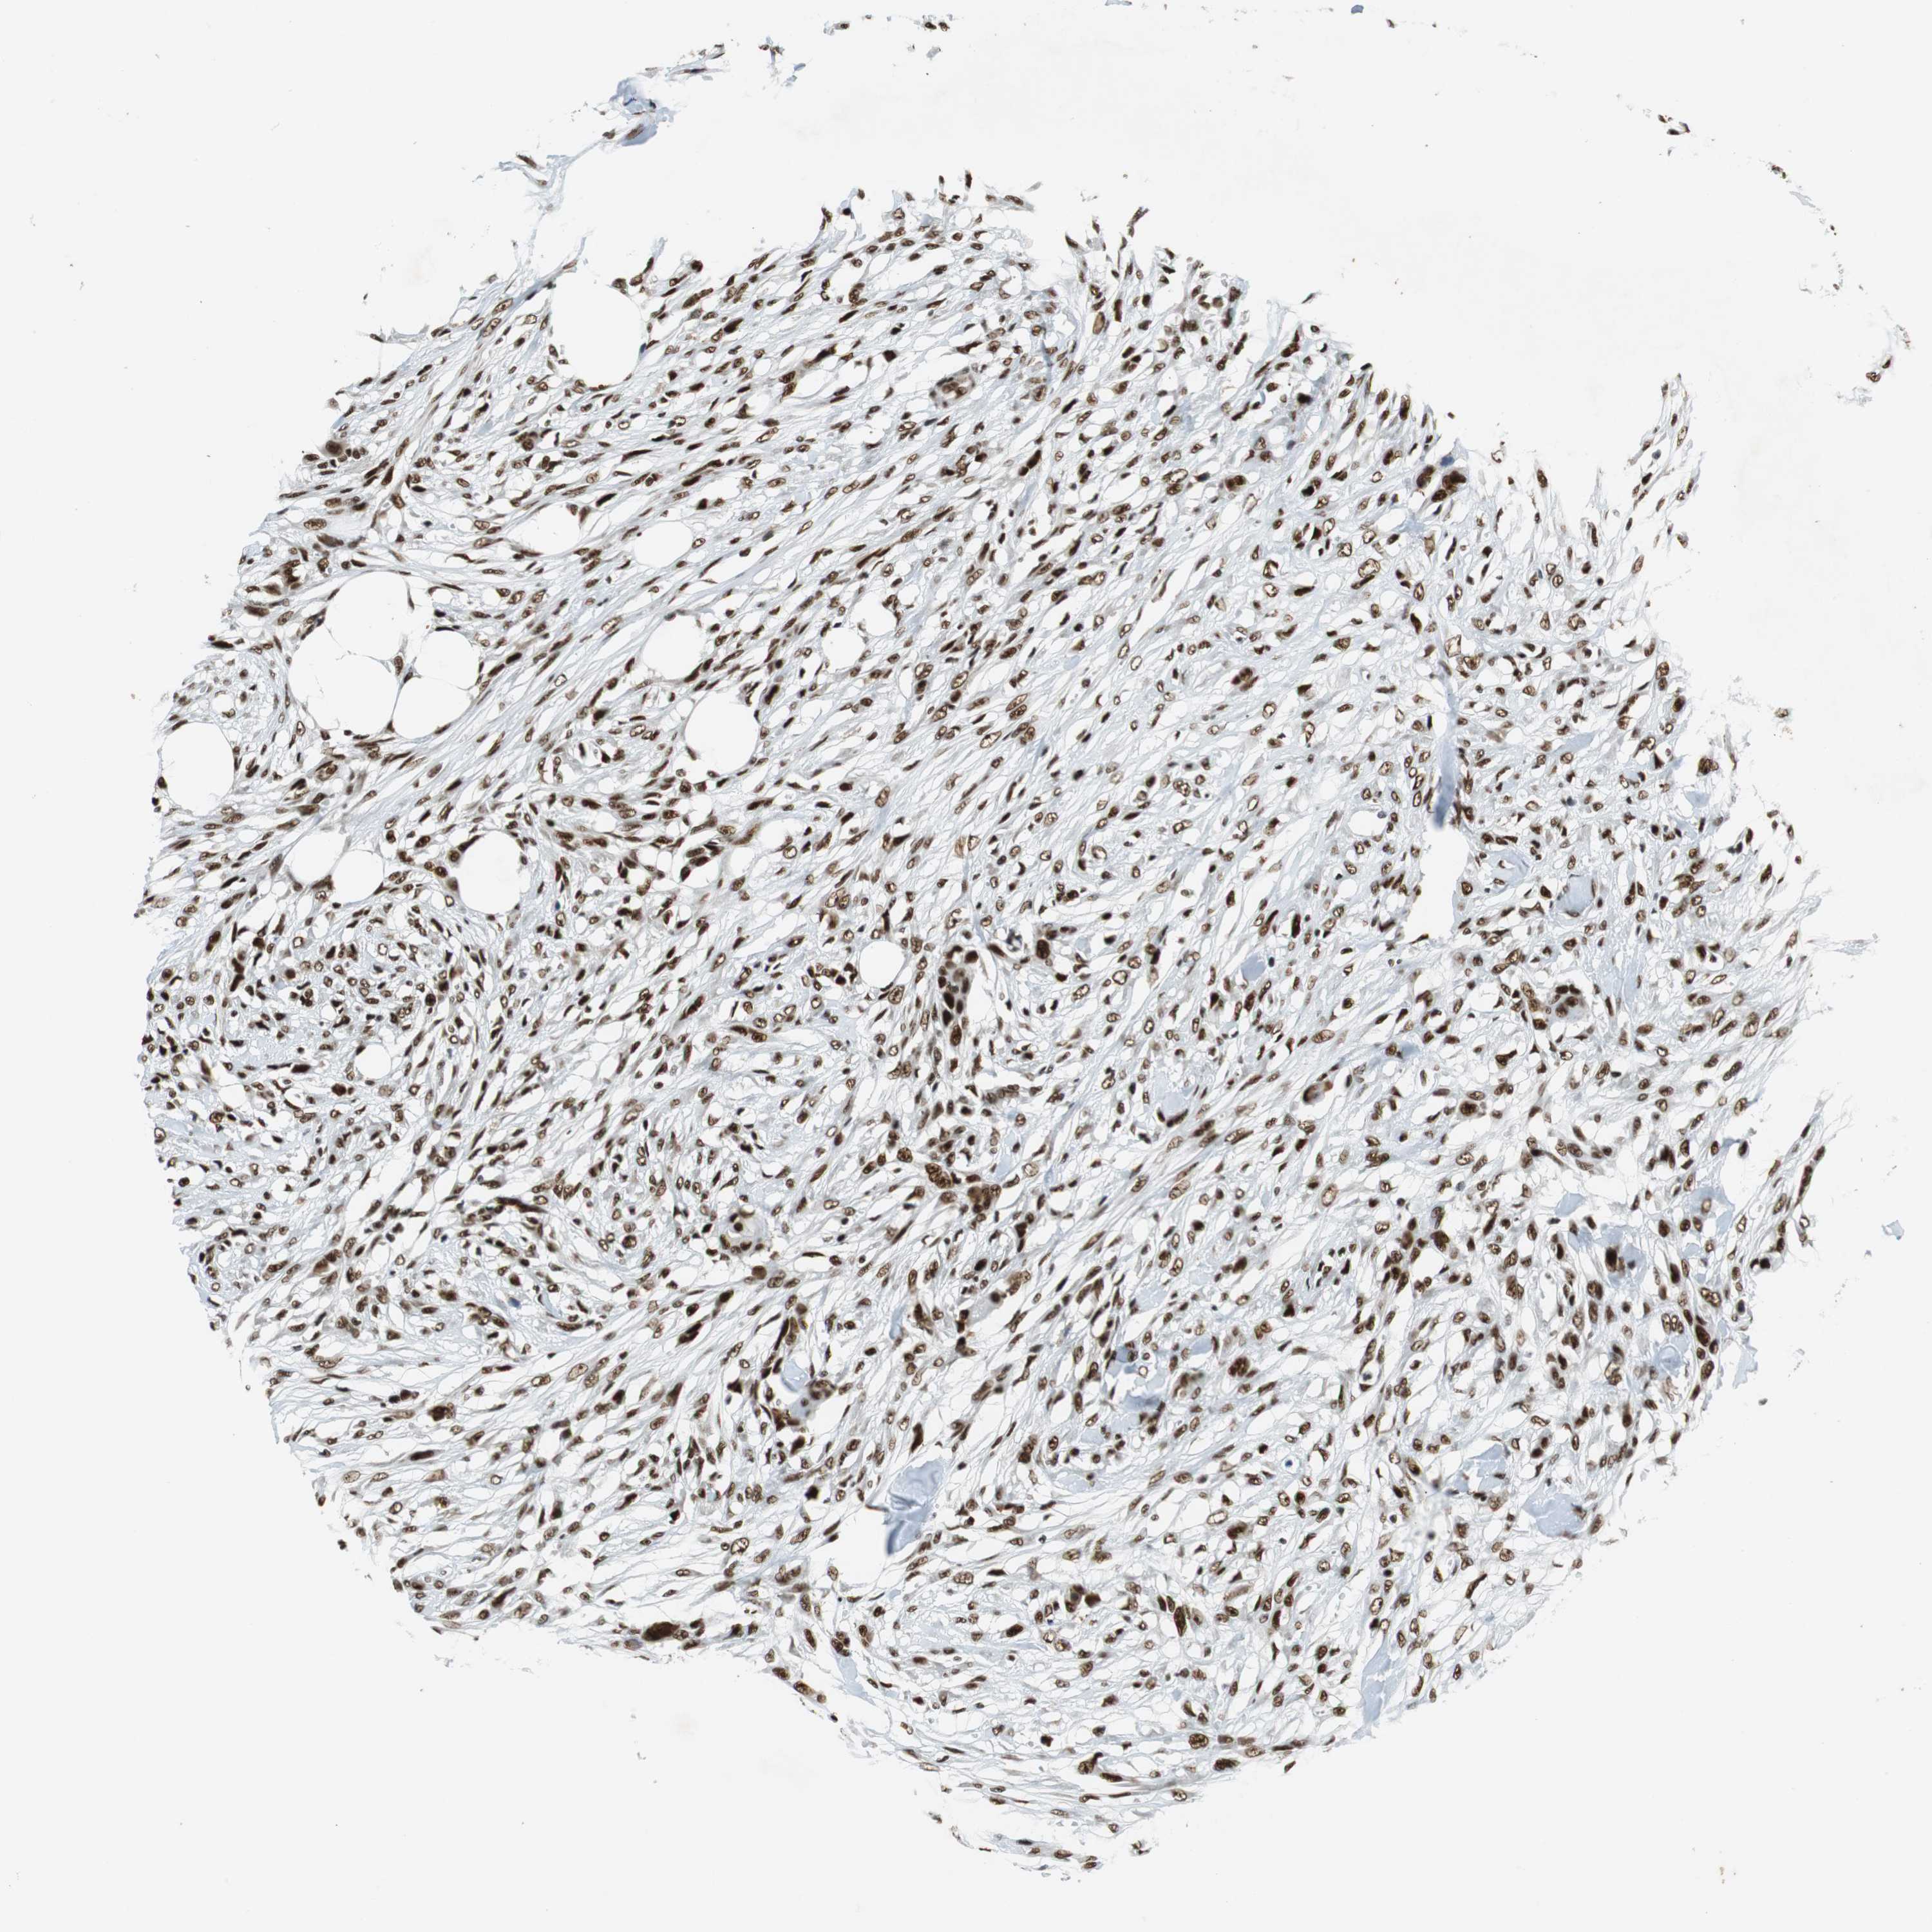

CANCER SKIN CANCER Show tissue menu

Basal cell and squamous cell cancer

SKIN CANCER - Protein expressioni

A mouse-over function shows sample information and annotation data. Click on an image to view it in a full screen mode. Samples can be filtered based on level of antibody staining by selecting one or several of the following categories: high, medium, low and not detected. The assay and annotation is described here.

Each image is clickable and will lead to virtual microscopy that enables deeper exploration of all samples and also displays staining intensity scores, fraction scores and subcellular localization as well as patient and tissue information for each sample.

Antibody CAB005167

Squamous cell carcinoma, NOS

Squamous cell carcinoma, metastatic, NOS